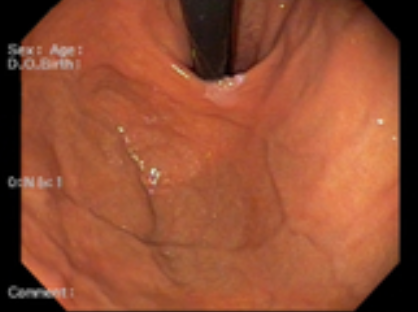

위내시경 검사는 위나 십이지장, 식도를 내시경 카메라로 살펴보는 검사로 평소 소화가 잘 되지 않거나 더부륵함, 메스꺼움, 복통, 속 쓰림, 구토 증상 등이 있다면 위염, 역류성식도염, 위용종, 위궤양, 위출혈, 십이지장질환, 위암, 식도암 등이 있을 수 있으므로 꼭 해보는 것을 권장드립니다.

최근에는 20~30세대 사이에서도 위암 발병률이 높아지고 있기 때문에 증상이 없더라도 정기적으로 위내시경 검사를 하는 것이 좋습니다. 특히 우리나라는 40세 이상 성인의 경우 2년에 한 번씩 위내시경 검사를 받을 수 있도록 국가에서 건강 검진을 실시하고 있으니 빼먹지 말고 꼭 받아보시기 바랍니다.

위내시경 검사의 방법은 수면과 비수면으로 진행되는데 비수면 위내시경 검사의 소요 시간이 5분~10분 정도밖에 걸리지 않아 빠르고 간편합니다. 비수면 위내시경 검사의 경우 직접 본인의 위 상태를 직접 눈으로 볼 수 있어 조금 더 위 건강에 신경 쓸 수 있다는 장점이 있습니다.

반면 수면 내시경의 경우 소요 시간이 30~50분 정도 걸린다고 봐야 합니다. 두 위내시경 검사 모두 전처치로 시행 10분~20분 전에는 위장관운동 억제제, 기포제거제를 먹고 인두 국소마취스프레이를 시행 후 검사에 들어갑니다.

위내시경 검사 중 조직검사를 통해 헬리코박터 감염 여부도 확인할 수 있습니다. 헬리코박터 파일로리 균 검사의 경우 1~2일이 지나면 결과를 알 수 있고, 조직 검사의 경우 7일에서 10일 정도 후 감염여부를 알 수 있습니다. 한 의료기관에서 위내시경 검사를 받았다면 2년 뒤에도 같은 병원에서 정기적으로 진행하는 것이 환자한테 좋습니다.